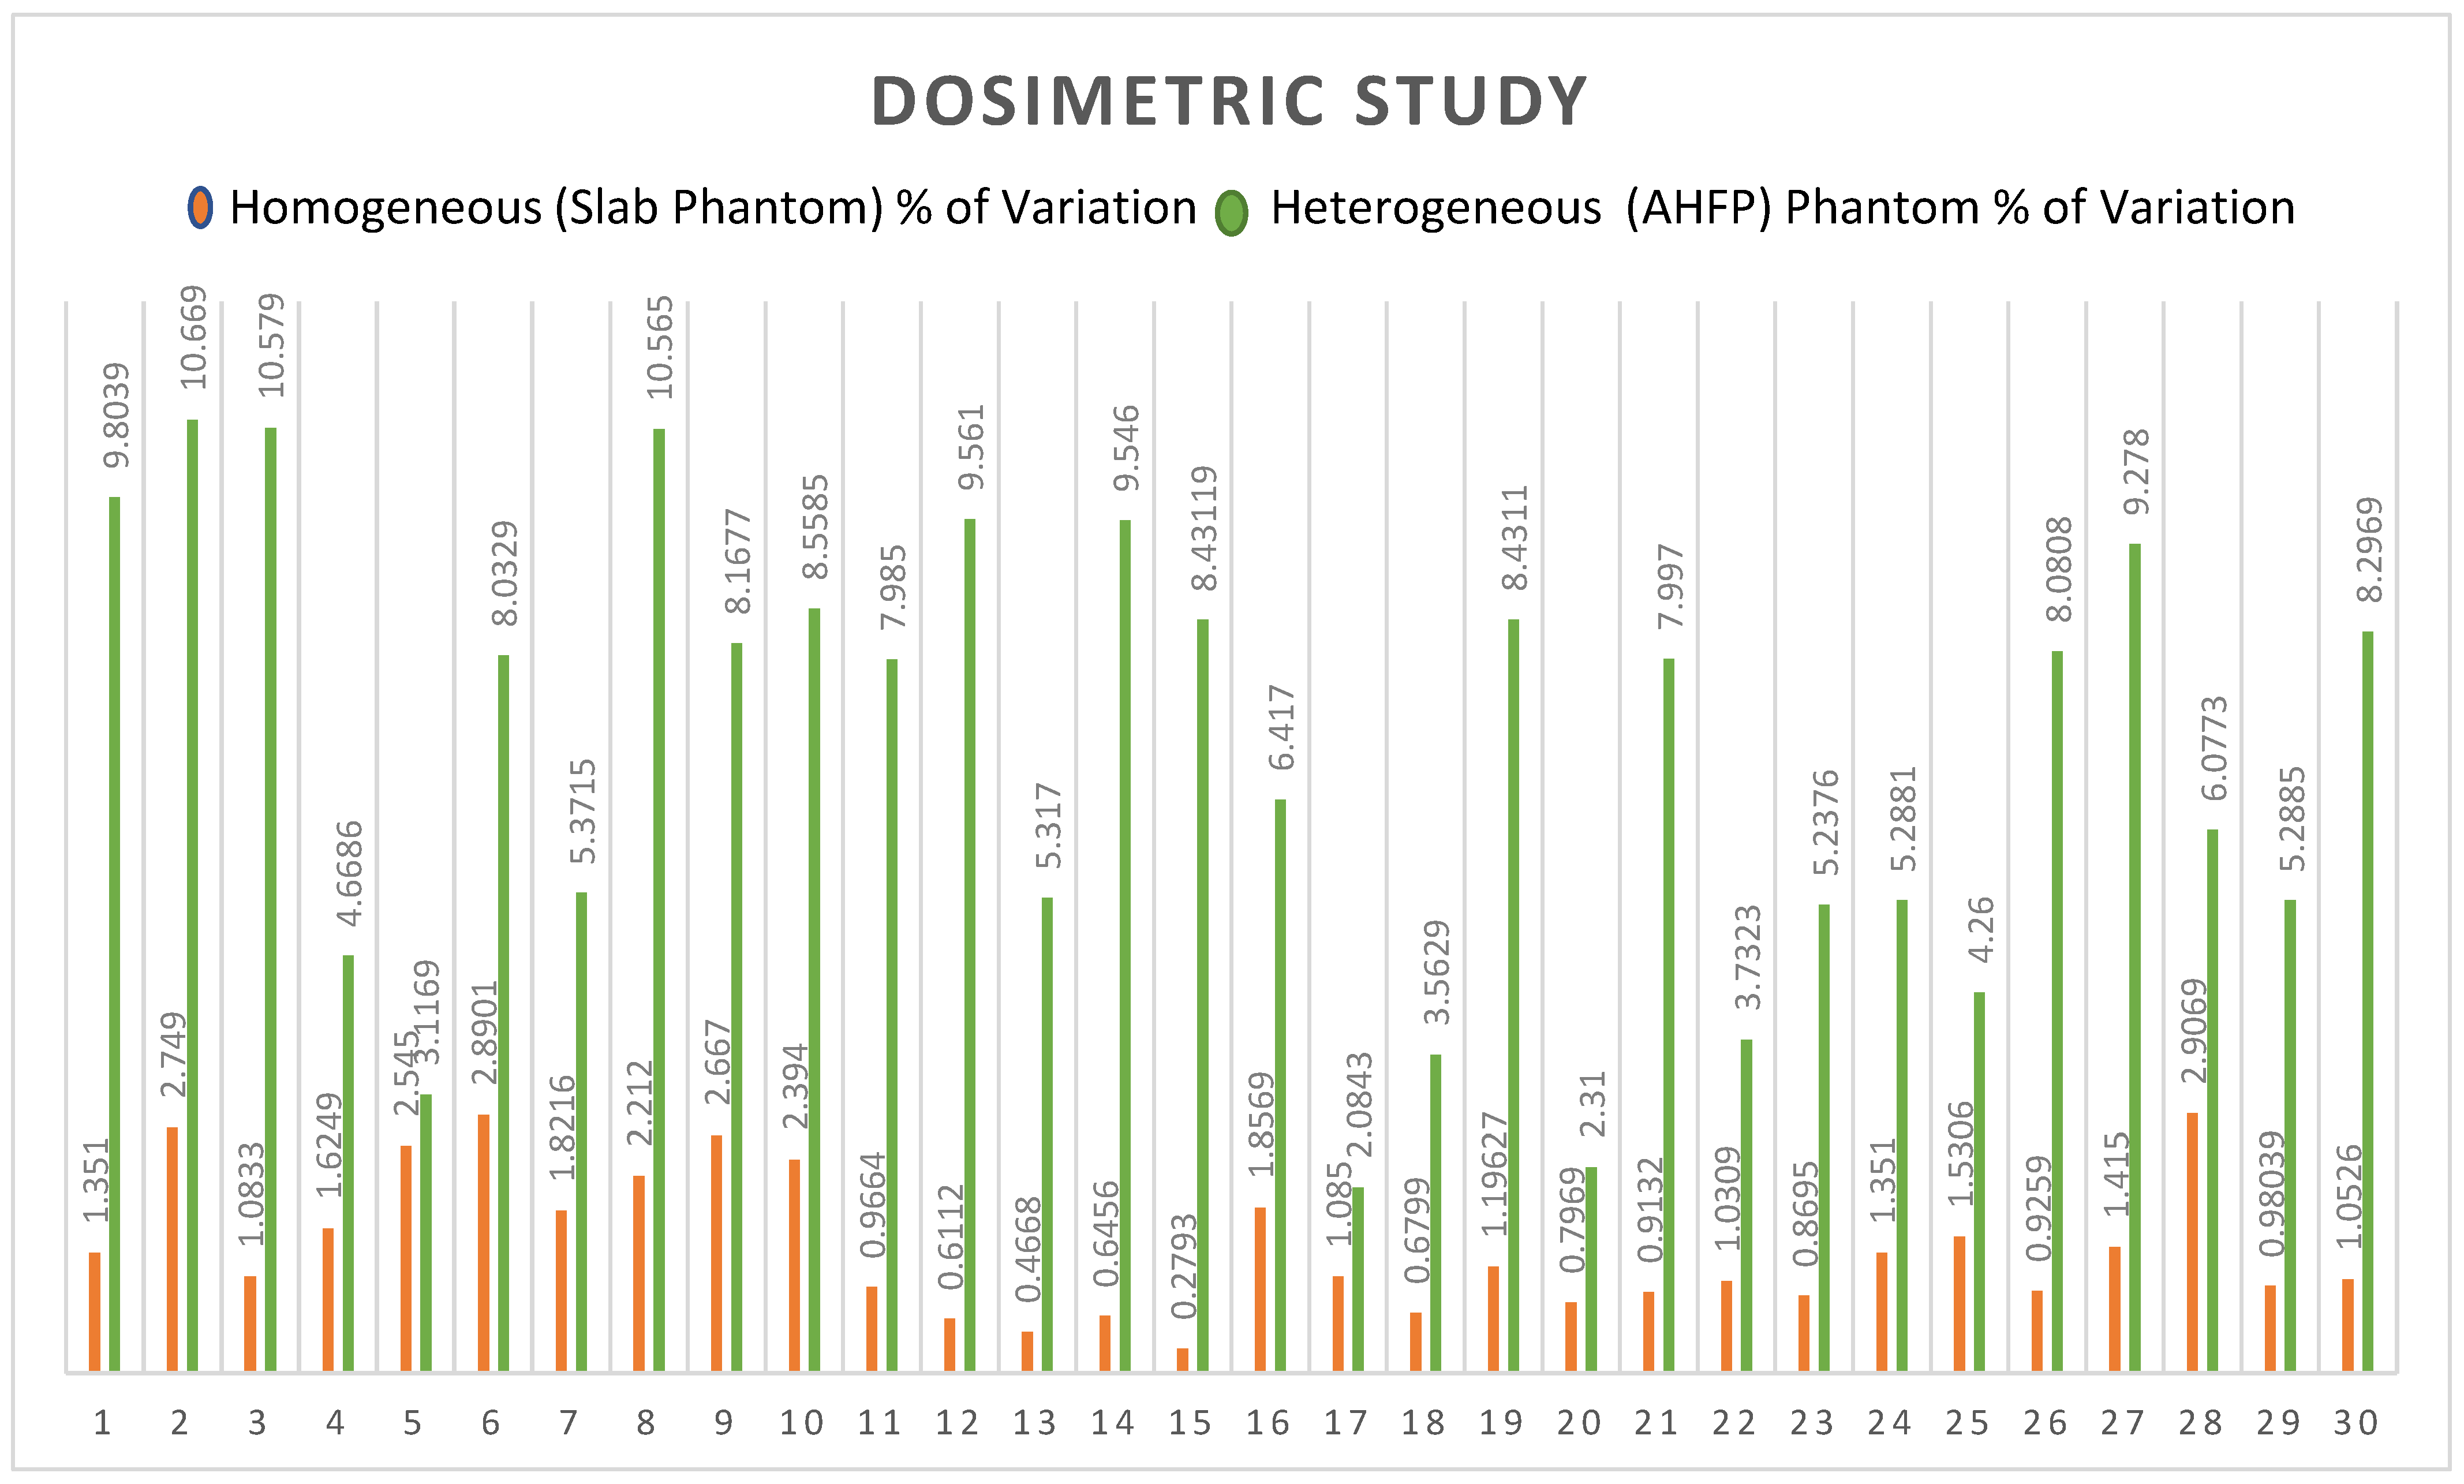

3. Results

4. Discussion